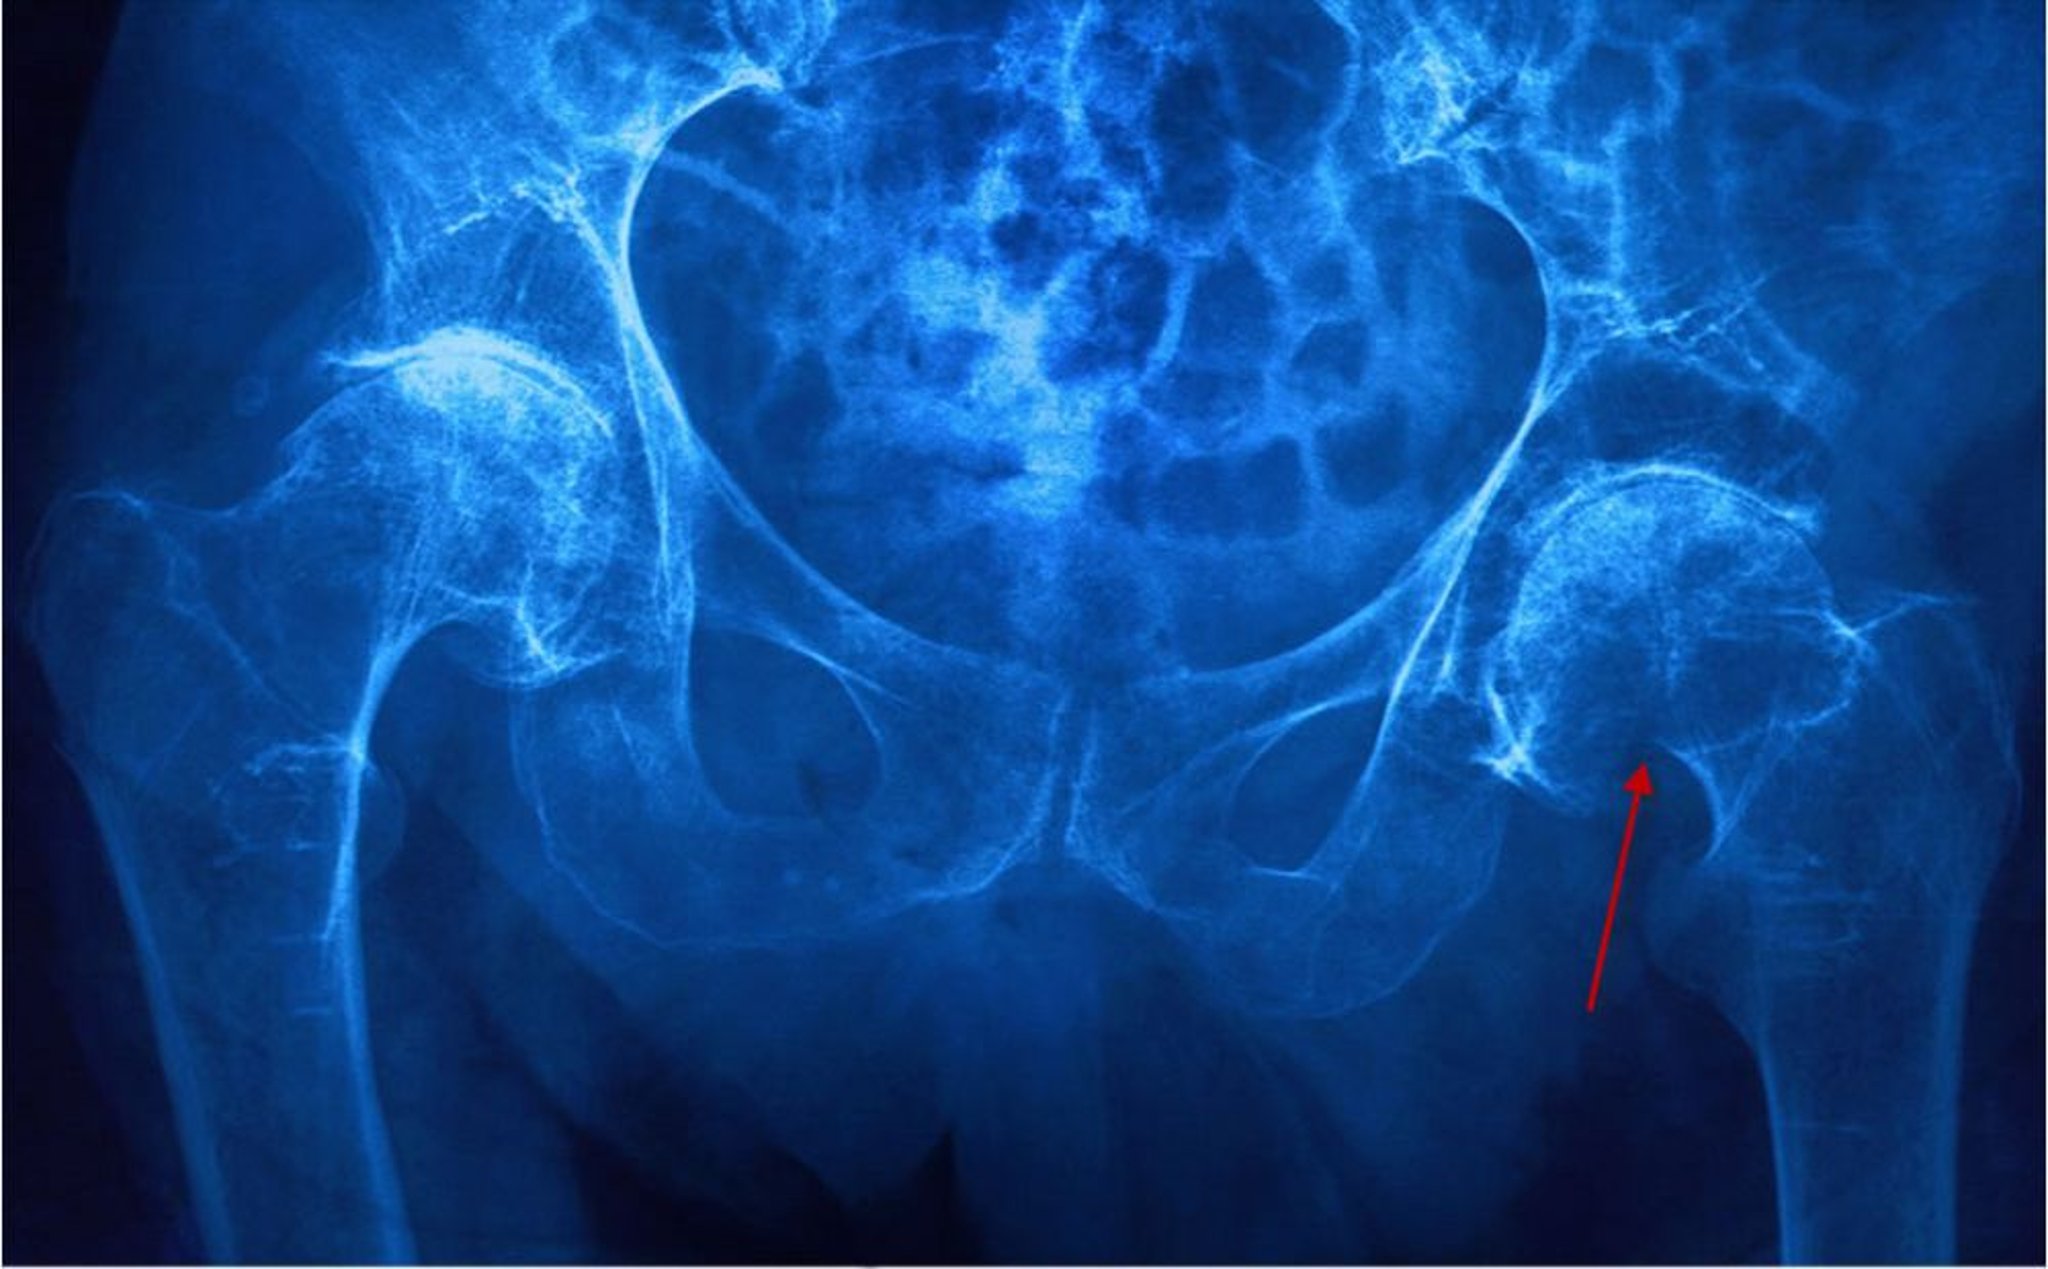

Fracturas del cuello femoral

Esta radiografía muestra una fractura del cuello femoral izquierdo (subcapital) evidenciada por un cuello femoral acortado y una interrupción de la corteza (flecha).